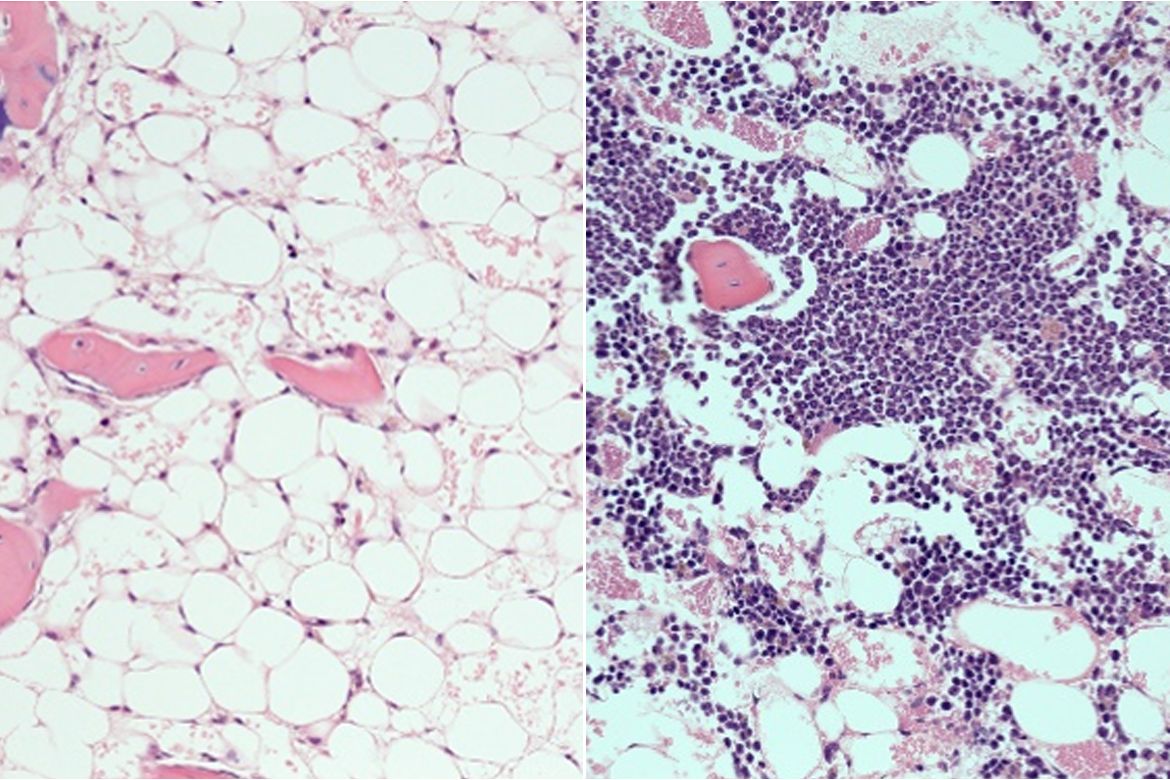

Chemotherapy and radiation generally suppress the activity of blood stem cells, and it typically takes weeks or months for the blood and immune systems to recover. In 2014, Chute and his colleagues discovered that PTP-sigma is also present on blood stem cells, and that its role in blood stem cells is similar to its function in neurons. In that study, the scientists found that in mice with a PTP-sigma gene deficiency, blood stem cells regenerated faster after they were suppressed by radiation.

Of the mice that received high doses of radiation, nearly all of the mice that were given DJ009 survived; more than half of those that did not receive the PTP-sigma inhibitor died within three weeks.

In mice that received chemotherapy — at doses approximating those used in people with cancer — mice that didn’t receive DJ009 had dangerously low levels of white blood cells and neutrophils, the cells that fight bacteria, after two weeks; in mice treated with the PTP-sigma inhibitor, white blood cell counts had already recovered to normal levels.